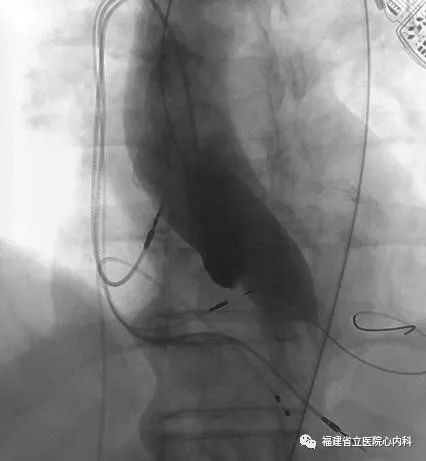

该病例是TYPE0型二叶瓣,瓣叶增厚伴极重度钙化,同时升主动脉增宽且为横位心,导致输送系统通过主动脉弓及瓣膜口难度明显增加,而且瓣上存在限制结构,瓣膜移位风险高,术中手术团队默契配合,输送系统顺利通过主动脉弓及狭窄的瓣口,Venus A-L26瓣膜定位精准释放,达到术前预期锚定位置,最终效果佳。

球囊预扩张

植入L26瓣膜